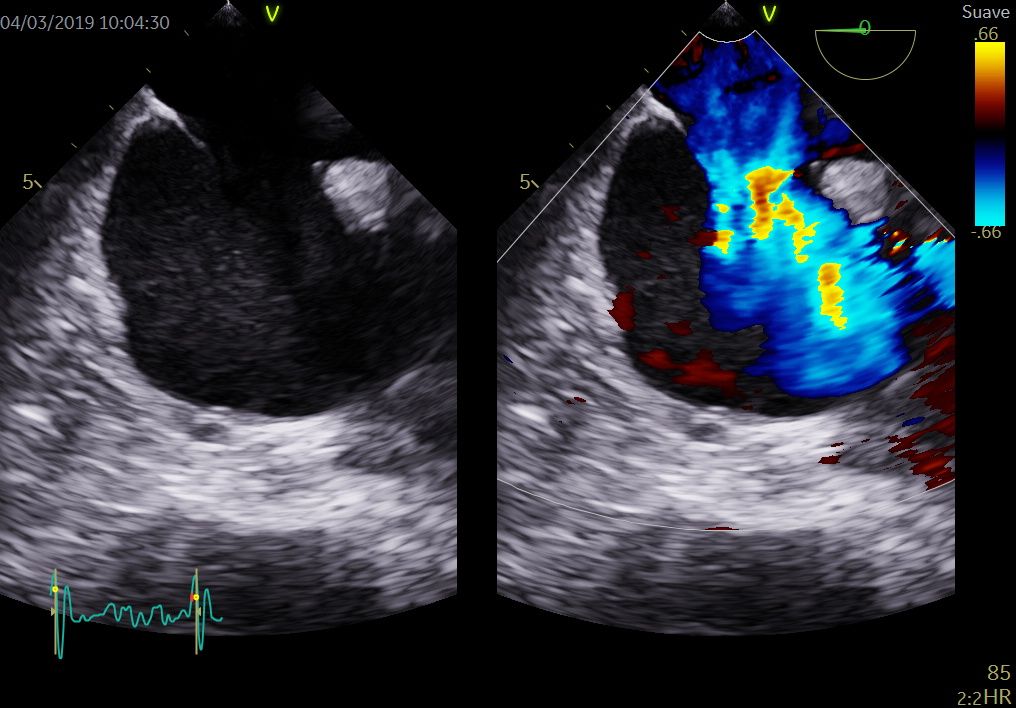

La Unitat ofereix una carta de serveis d'imatge cardiovascular de màxim nivell, que dona cobertura a tots els pacients adults i pediàtrics amb patologia cardíaca de la Regió Sanitària Girona. L'oferta assistencial inclou estudis d’ecocardiografia transtoràcica i transesofàgica en 2D, 3D i 4D, així com ecocardiografia d'estrès, tant farmacològic com d'esforç físic. També incorpora l'estudi i el seguiment de les cardiopaties congènites de l'adult i de l'infant.

La Unitat està acreditada per la Societat Europea de Cardiologia com a laboratori avançat en la realització d'ecocardiografia transtoràcica, transesofàgica i d'estrès.